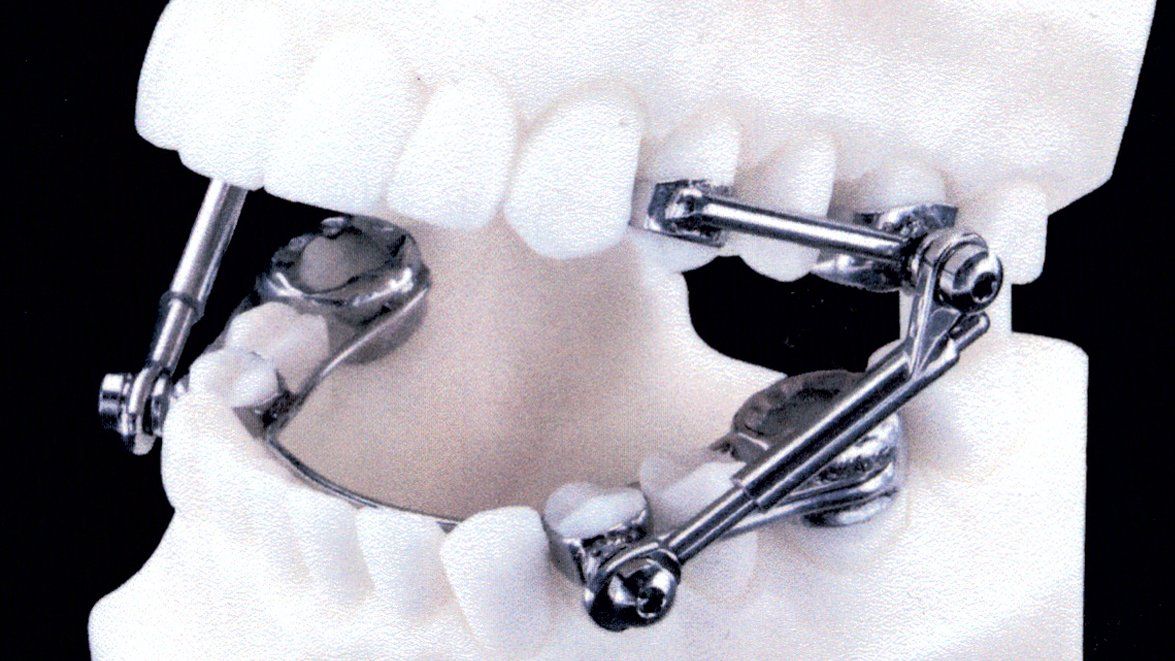

L'ortodonzia del bambino si divide in una fase ortopedica in cui

si migliora la situazione della forma delle arcate dentali

sfruttando le cartilagini presenti nei mascellari stessi e una parte ortodontica vera e propria con spostamento dei denti.